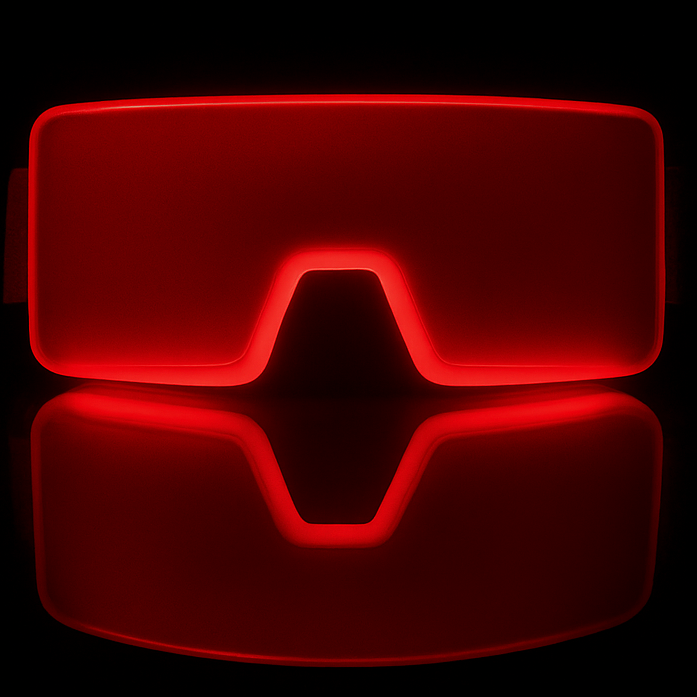

WaveFront Alignment:

Park et al. used a 590→830 nm sequence at slightly higher diffuse fluence; the outcomes align with PBM’s known mitochondrial and inflammatory pathways. The Spectral WaveFront uses 670 nm and 810 nm with ocular-specific geometry and lower, non-contact fluence—supporting similar biologic mechanisms relevant to dry eye, eyelid-margin metabolism, and tear-film stability.